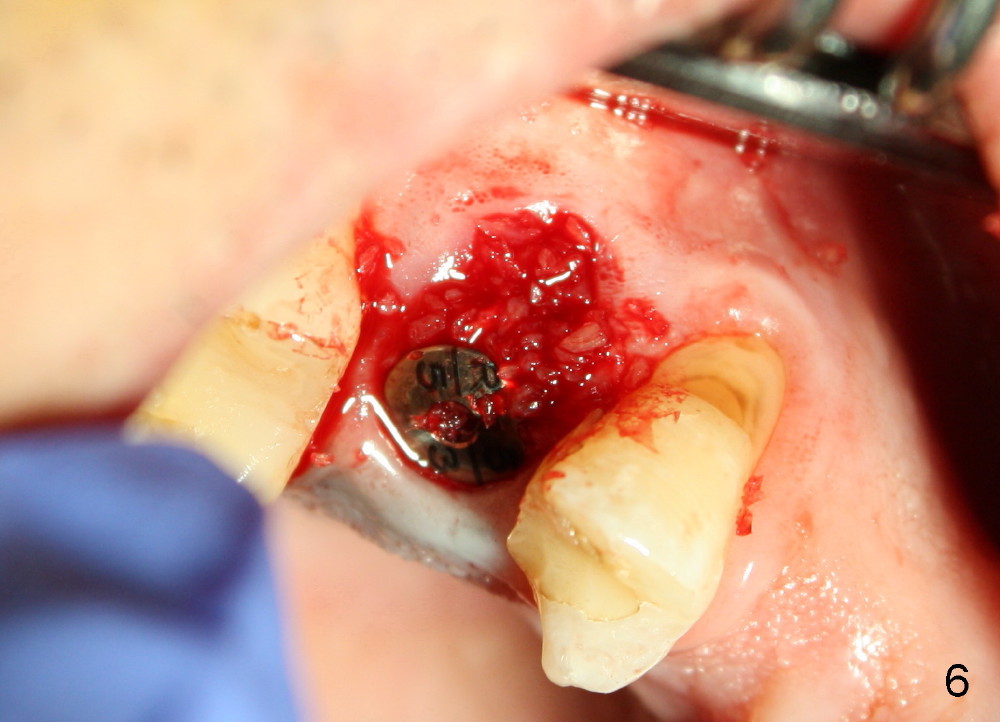

A 51-year-old man has several missing teeth in the maxilla restored by a partial denture. The tooth #4 fractures (Fig.1) and is planned to be restored by an implant (Fig.2 design: 4.5x14 mm). Immediately post extraction, osteotomy is initiated by a 2.0 mm pilot drill at the depth of 14 mm (3 mm into new bone, Fig.3). Finally a 4.5x14 mm SM (submerged) implant is placed with insertion of a 5.2x5(3) mm healing abutment (Fig.4). Mixture of autogenous bone and demineralized cortical allograft is placed in the gap between the buccal plate and the implant/abutment (Fig.6), covered by collagen membrane (Fig.7 M; P: partial denture). In fact the membrane is fixed between the implant and the healing abutment lingually. The wound is finally covered by perio dressing (Fig.5 ^). The patient returns 5 days postop. The perio dressing is removed unintentionally. It appears that the membrane has started to be resorbed (Fig.8).